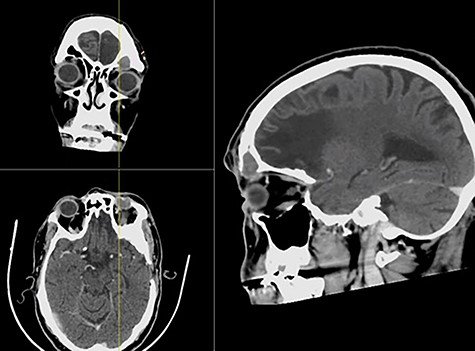

The left eyelid swelling was causing inferior globe dystopia with mild tenderness on palpation, but no redness, fluctuation or cutaneous changes (Fig. 1). The extraocular muscle movements were intact, except for limited left supraduction due to the eyelid swelling. The pupils were equal and reactive, and visual acuity and color vision were normal. Transnasal endoscopic examination was unremarkable bilaterally. Contrasted sinus computed tomography (CT) scan showed an expanding left frontal sinus hyperdense opacification with peripheral enhancement and extension to the left orbit (Fig. 2). Magnetic resonance imaging (MRI) showed a loculated mucocele in the left frontal sinus with hypertense T1 signal and extension to left orbit but no intracranial extension (Fig. 3).

CT with contrast showing a complete left frontal sinus opacification with an inferior bony defect and extension to the left globe and obstruction of the frontal sinus drainage pathway in coronal (a), axial (b) and sagittal (c) views.